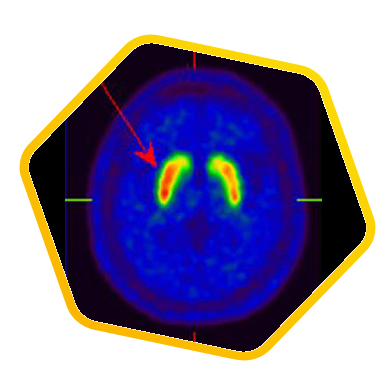

脑神经科

![]() [C-11] Raclopride |

![]() [F-18] DOPA |